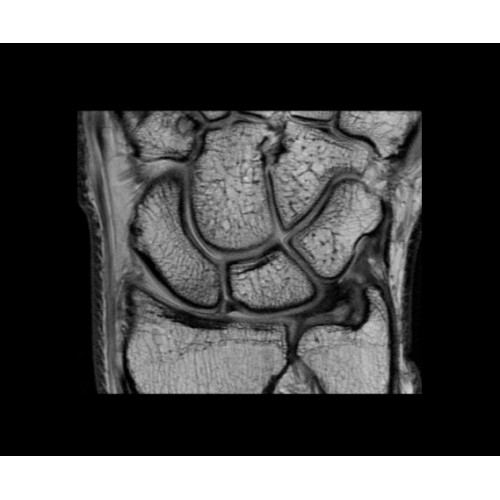

В систему SIGNA PET/MR встроены запатентованные детекторы кремниевого фотоумножителя (SiPM) и сверхчувствительные кристаллические сцинтилляторы на основе лютеция толщиной 25 мм. Благодаря этому обеспечивается исключительная чувствительность и возможность использования времяпролетной диагностики (TOF).

Кроме того, в результате использования технологии TOF и инновационной технологии реконструкции Q.Clear вы сможете добиться прекрасного соотношения сигнал/шум. А благодаря технологии нулевого времени эхо (ZTE) визуализировать костную структуру без ионизирующего излучения. Все эти разработки для улучшения качества сканирования и точности анализа помогут вам использовать весь потенциал ПЭТ/МРТ.

• МРТ с функцией нулевого времени эхо (ZTE) отличается точностью, возможностью персональных настроек и отсутствием ионизирующего излучения. Она приходит на смену традиционному исследованию на основе рентгеновского излучения. МРТ с функцией нулевого времени эхо (ZTE) на базе SIGNA ПЭТ/МРТ является более надежной и быстрой по сравнению с системами, использующими сверхмалое время эхо (UTE).